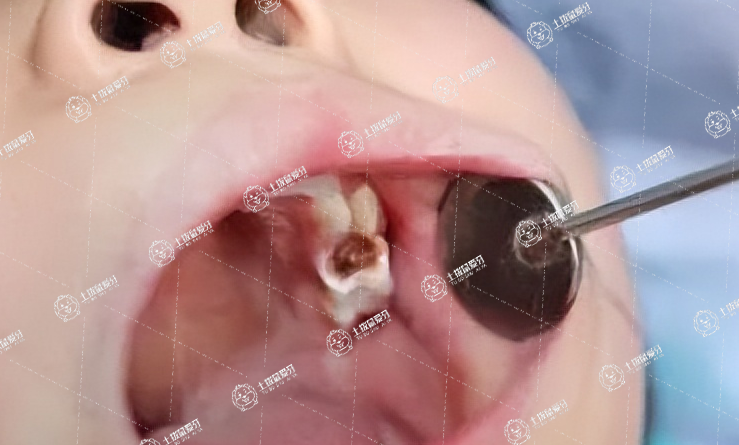

兒童期是牙齒發(fā)育的重要階段,有些孩子卻在此時出現(xiàn)了各種齲齒蛀牙的情況,給身心健康造成極大的影響,作為家長看在眼里疼在心里,想要及時給孩子做補牙處理,當然,也會考慮:小孩補牙有必要補嗎?一起來了解一下。

兒童肯定應(yīng)該要補牙的,如果說不補牙的,那蛀牙只會越來越深,這樣疼痛會加重,對兒童的飲食,包括生活都會造成非常大的影響。

另外如果說這顆是乳牙,雖然會更換,但是如果說牙根發(fā)炎的,也是會影響恒牙胚的,到時候會導致恒牙的萌出異常,這個危害也是非常大的。

所以說兒童肯定是越早補牙損傷越小,一個是沒有痛苦,還有一個也可以盡早恢復(fù)功能和使用。

小孩兒有牙洞,最好是補洞,如果是齲齒和平時口腔衛(wèi)生習慣有關(guān),治療齲齒的主要方法是:充填,將齲壞組織去除去干凈,做成一定的洞型,清洗消毒以后用充填材料,恢復(fù)牙齒缺損的外形,以免影響鄰牙。